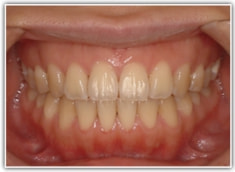

治療後(1年8ヶ月後)

動的治療後セファロ分析

良好な咬合関係が認められます。